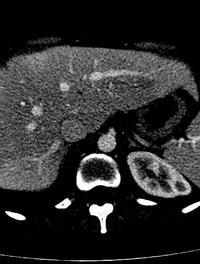

Le carcinome hépatocellulaire (CHC) représente environ 90 % des cancers primitifs du foie. Sa prévalence ne cesse d’augmenter à travers [...]

Des métastases hépatiques sont détectées chez 40 à 50 % du million de patients chez lesquels un cancer colorectal est diagnostiqué [...]